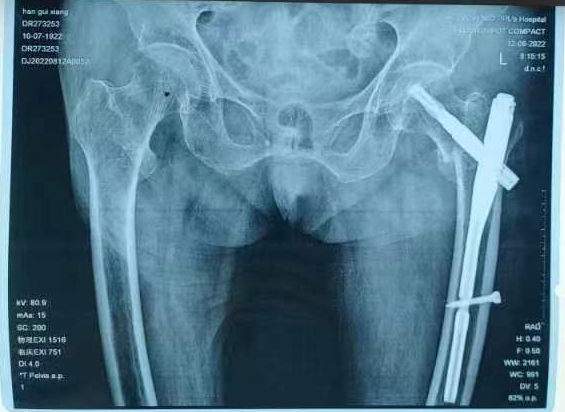

百岁老人在家不慎跌倒,随即出现左髋关节活动受限,不能活动。老人被家属带到当地县人民医院行左髋关节X线片检查示:左侧股骨转子间骨折(A2型)当地医院考虑患者年纪较大,身体条件差、手术风险高,不建议为患者行手术治疗。 患者听说焦作市第二人民医院骨科三区一位主任技术非常好,因此患者家属抱着试试的态度,带患者来我院救治,并以“左侧股骨转子间骨折”收住骨科三区。

入科后,陈旭副主任(副主任医师)认真评估患者身体条件,积极纠正电解质紊乱,考虑患者年纪较大,长期翻身困难,容易并发多种卧床并发症,因此患者入院第二天即积极安排患者手术。入院第三天,在余进伟主任(主任医师)的指导及麻醉手术部刘有才主任麻醉团队严密监控患者生命体征下,陈旭副主任医师为患者顺利施行手术。 术后患者生命体征稳定,随即转入骨科三区普通病房。陈豪杰医师作为管床大夫,积极进行术后处理,进行精准补液维持循环电解质稳定,定期多次查房关心患者恢复情况,发现问题立即处理。在李德荣护理团队个体化、细致化、规范化、科学化的精心护理下,患者慢慢恢复健康。术后第二天,患者在床上即可自如翻身、左髋关节自如活动,而且疼痛消失。术后第三天,在陪护的搀扶下离开病床进行排便,术后第十天,患者康复出院。于是,便出现了文章开头的一幕。这份“特殊”的医师节“礼物”,既是百岁老人及家属表达对医护人员的浓浓感激之情,更是对医院服务品质的认可和肯定,彰显出医患彼此间的信任与和谐,正是这份信任与和谐激励着我院医务人员,一如既往为患者康复做出最大努力! 股骨转子间骨折是最常见的髋部骨折,七十岁以上的人群发生率最高,一般由低能量损伤,如跌倒所致。股骨转子间骨折已经成为最重要的公共健康问题之一,尽管该部位血供丰富,骨折容易愈合,但老年患者大多合并内科疾病基础,长期卧床过程中容易引发各种并发症,如血栓栓塞症、坠积性肺炎、褥疮等,严重威胁着老年患者的生命健康,因此股骨转子间骨折又被称为“人生最后一次骨折”,此外患股骨转子间骨折的老年因髋关节活动受限,翻身及二便困难,增加了家属的护理难度,因此早期手术行股骨转子间骨折闭合复位髓内钉内固定术,已经成为了共识。术后老年髋部骨折即可获得稳定,出院方便居家护理,减轻老年患者痛苦,避免及减少因长期卧床造成VTE、坠积性肺炎以及褥疮等发生率。超高龄患者髋部脆性骨折,在严格评估手术风险及稳定生命体征,术后规范化、细致化的护理以及维持电解质、心肺功能稳定,尽可能的实现早手术!早康复!早出院!